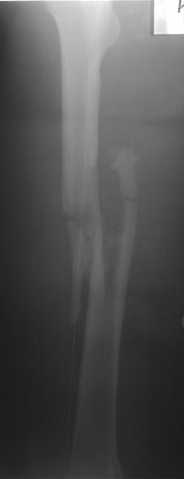

Р.S. Привожу клинический пример больного с огн. переломом бедра Густилло- Андерсон 111 А

В нашем случае 21 летний боец уличного фронта, фиксацию провели на следующий день, зафиксирован интрамедуллярным штифтом. Не стали делать первичную хирургическую обработку точечной раны, зафиксирован как есть. Клинические снимки:

Конечно, наш случай не эталон, возможно, на месте вам виднее, может быть, нет необходимости ориентироваться на зарубежные ссылки, если получается лечить аппаратом Илизарова на месте, почему нет? Необходимо посмотреть собственный арсенал, чем фиксировать, и какая теория, иначе любой отличный метод можно превратить в источник остеомиелита.